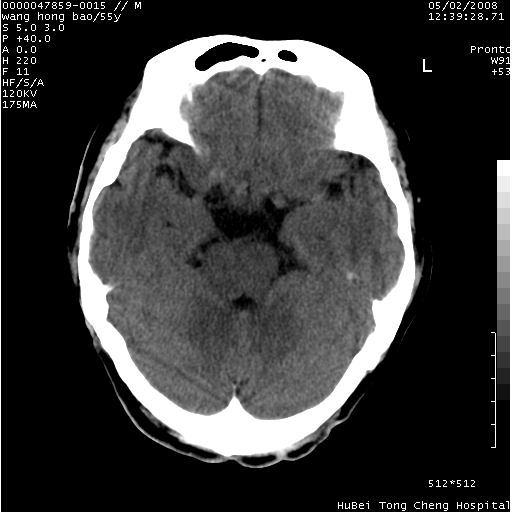

以下是引用dyqct在2008-5-3 23:36:00的发言:[br]桥前池区可疑蛛网膜囊肿。其它未见明显异常。建议做mri。

以下是引用qiushi在2008-5-4 10:10:00的发言:[br]鞍上池前缘突出影为双侧额叶直回;箭头所指为双侧正常之人字缝.[br]桥前池区可疑表皮样囊肿或蛛网膜囊肿,必要时mri

以下是引用zjzjr在2008-5-4 14:50:00的发言:[br]桥前池区可疑蛛网膜囊肿。其它未见明显异常。建议做mri。